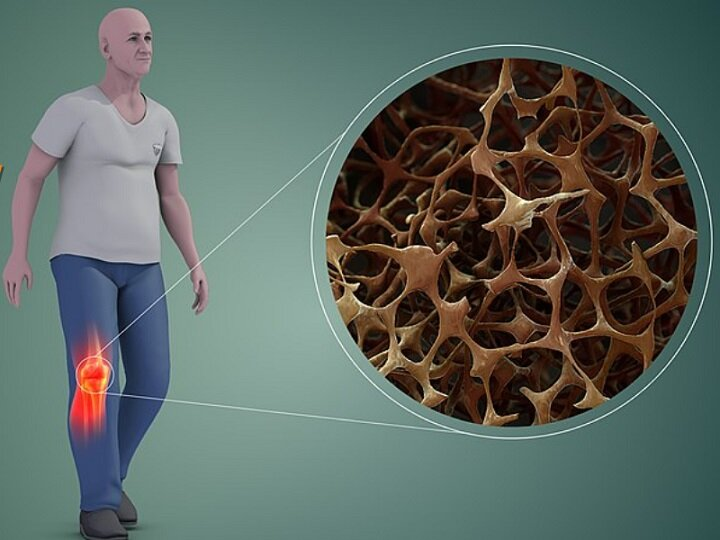

پوکی و نرمی استخوان از بیماریهای شایع استخوانی هستند که با کاهش تراکم و استحکام استخوانها، بهویژه در سنین بالاتر، میتوانند استقلال حرکتی افراد را تهدید کنند و تغذیه نادرست نقش مهمی در بروز و تشدید این عارضهها دارد.

به گزارش لوح خبر، پوکی و نرمی استخوان از مشکلاتی هستند که زنان و مردان در سنین میانسالی و سالمندی با آن مواجه میشوند و خطر زمینخوردن و ناتوانی حرکتی را افزایش میدهند. کلسیم یکی از مهمترین عناصر در حفظ سلامت استخوانهاست و کمبود آن به کاهش تراکم استخوان و بروز پوکی استخوان منجر میشود. حدود ۹۹ درصد کلسیم بدن در استخوانها و دندانها ذخیره شده و دریافت روزانه آن برای بزرگسالان حدود ۱۰۰۰ میلیگرم است؛ این میزان برای زنان بالای ۵۰ سال و مردان بالای ۷۰ سال به ۱۲۰۰ میلیگرم در روز افزایش مییابد.

دکتر منصور رضایی، متخصص تغذیه، با اشاره به تفاوت پوکی و نرمی استخوان توضیح میدهد: پوکی استخوان یا استئوپروسیس (Osteoporosis) بیشتر وابسته به سن، جنس و وضعیت هورمونی است و شیوع بالاتری در زنان سالمند، بهویژه افرادی که دچار اختلالات هورمونی یا بیتحرکی و استرس مزمن هستند، دارد. در این عارضه، کاهش پروتئین ناشی از مشکلات هورمونی نقش پررنگتری نسبت به کمبود املاح دارد.

وی درباره نرمی استخوان نیز میگوید: نرمی استخوان یا استئومالاسی (Osteomalacia) بیشتر ناشی از کمبود املاحی مانند کلسیم و روی است و در کودکان به شکل راشیتیسم بروز میکند. این بیماری اغلب با کمبود ویتامین D مرتبط است و میتواند باعث تغییر شکل استخوانها از جمله پای پرانتزی شود.